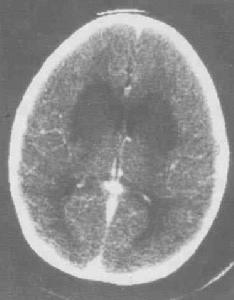

在嚴重的病例腦電圖檢查,可四川發現廣泛高度不正常的高波幅慢波及在此背景上的局灶性,改變相同影像學檢查(電子計算機斷層及磁共振檢查),可顯示腦水腫壞死灶(顳葉及額葉壞死灶見於單純皰疹腦炎)和主要基因位於腦白質的脫髓鞘病灶(急性播散性腦脊髓炎),